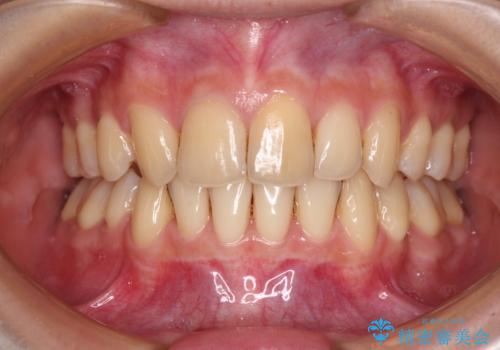

八重歯を改善 目立たないワイヤー装置での矯正治療

前から5番目の乳歯は、後続永久歯である小臼歯と比べて幅径が大きいため、移動に時間がかかりましたが、きれいに仕上げることができました。